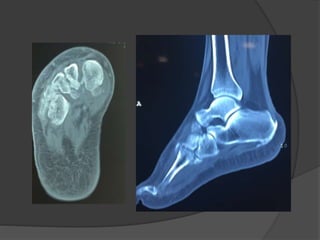

Case 1: A“healthy” 50 year old

Fell off a 3 ft high parapet

c/o pain, inability to bear weight on the right

foot

Initial radiographs

6 weeks later the cast was taken off, unable to bear

weight

Diagnosis

?

Lisfranc fracture- dislocation

Bony or ligamentous injury involving the tarsometatarsal